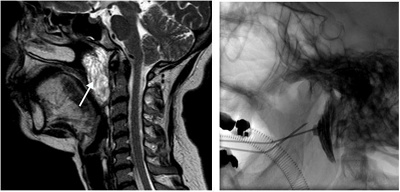

Behandlung einer low-flow Gefässmalformation im Rachenbereich (Pfeil) mittels Direktpunktion mit einer feinen Kanüle und hierüber Einbringen von Verödungsmittel (Sklerosierung).